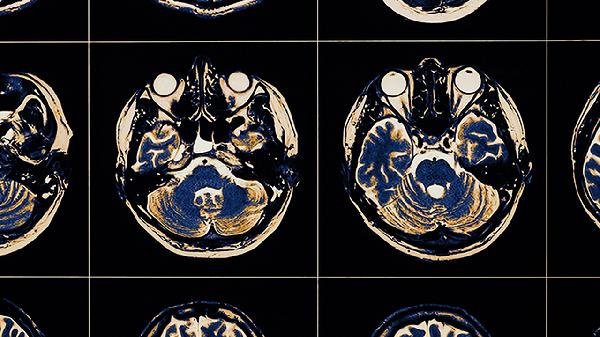

脑血栓的症状表现有哪些 脑血栓的3个表现很凶险

脑血栓的典型症状包括突发性偏瘫、言语障碍和意识模糊,其中急性大面积脑梗死、进展性卒中与脑疝形成属于最凶险的三种表现。